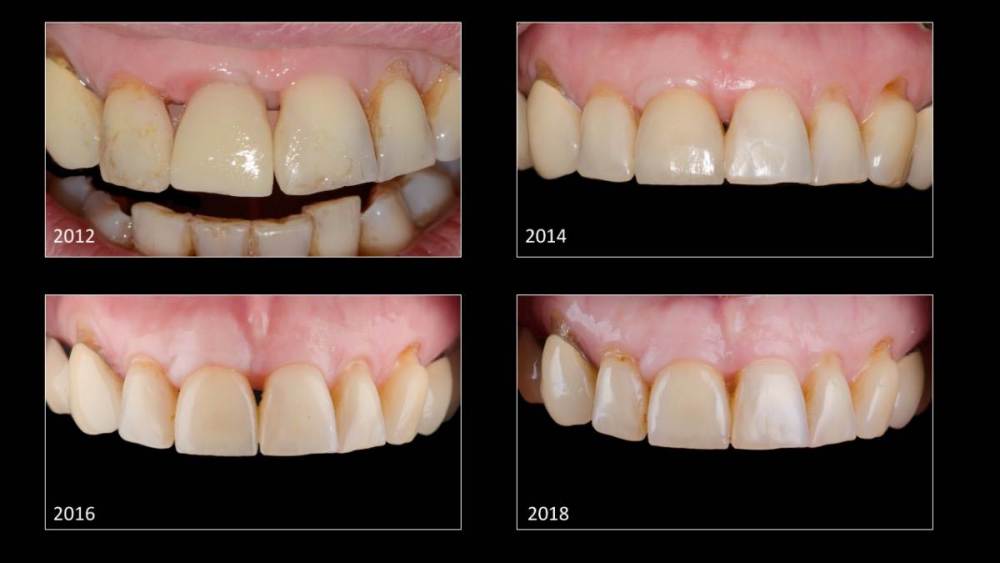

Владмир Опубликовано 20 марта, 2023 Автор Поделиться Опубликовано 20 марта, 2023 Здравствуйте коллеги. Работе 10 лет. Фото начальных этапов добавил 7 1 2 Ссылка на комментарий